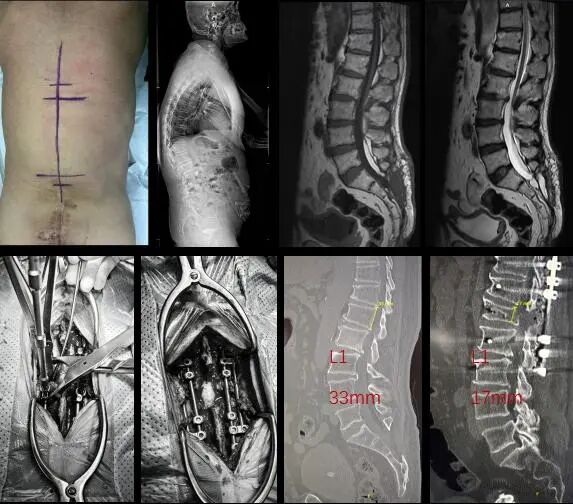

本次手术由齐鲁医院神经外科脊髓脊柱专业姜政主任医师团队联合脊柱外科矫形专业原所茂主任医师团队共同完成。患者为一名老年男性,腰骶部肿物4年余,双下肢麻木3年余,以右下肢为重,伴右下肢胀痛感,后逐渐出现行走不稳。于2023年4月于外院行骶管脂肪终丝切除+脊神经根松解术,2025年12月于原切口行脊膜膨出及脑脊液漏修补术。近半年来症状较前明显加重,自诉提臀困难,无法站立或行走,严重影响日常生活能力。

经医院神经外科、脊柱外科等多学科团队(MDT)严谨评估,并征得患者及家属知情同意后,团队决定采用脊柱缩短术进行治疗。与传统栓系松解术相比,该术式避免了对第一次及第二次手术部分脊髓及硬膜内结构的直接操作,显著降低神经损伤及脑脊液漏等并发症风险,尤其适用于复发性或复杂病例(如严重瘢痕粘连者)。此外,脊柱缩短术能够提供更持久的张力缓解,降低再栓系发生率,并在部分患者中兼具矫正脊柱畸形的作用,因此在成人及难治性脊髓栓系患者中展现出更稳定和可靠的临床疗效。

手术过程顺利,患者L1椎体由术前33mm缩短至17mm。术后,患者生命体征平稳,自述双下肢麻木较术前明显减轻。

脊髓栓系综合征是导致患者神经功能进行性损害的重要原因之一,传统松解术在部分复杂或复发病例中疗效受限且风险较高。脊柱缩短术通过降低脊髓纵向张力,实现对栓系状态的间接解除,从机制上更符合疾病本质,是当前治疗脊髓栓系的创新策略。此次将脊柱截骨缩短与精准内固定技术相结合,不仅提升了手术的安全性与稳定性,也为复杂及再手术患者提供了新的治疗选择。团队将继续依托医院多学科协作平台,整合神经影像、术中神经监测及康复评估等技术资源,为脊髓栓系患者提供全流程、个体化的综合诊疗方案。